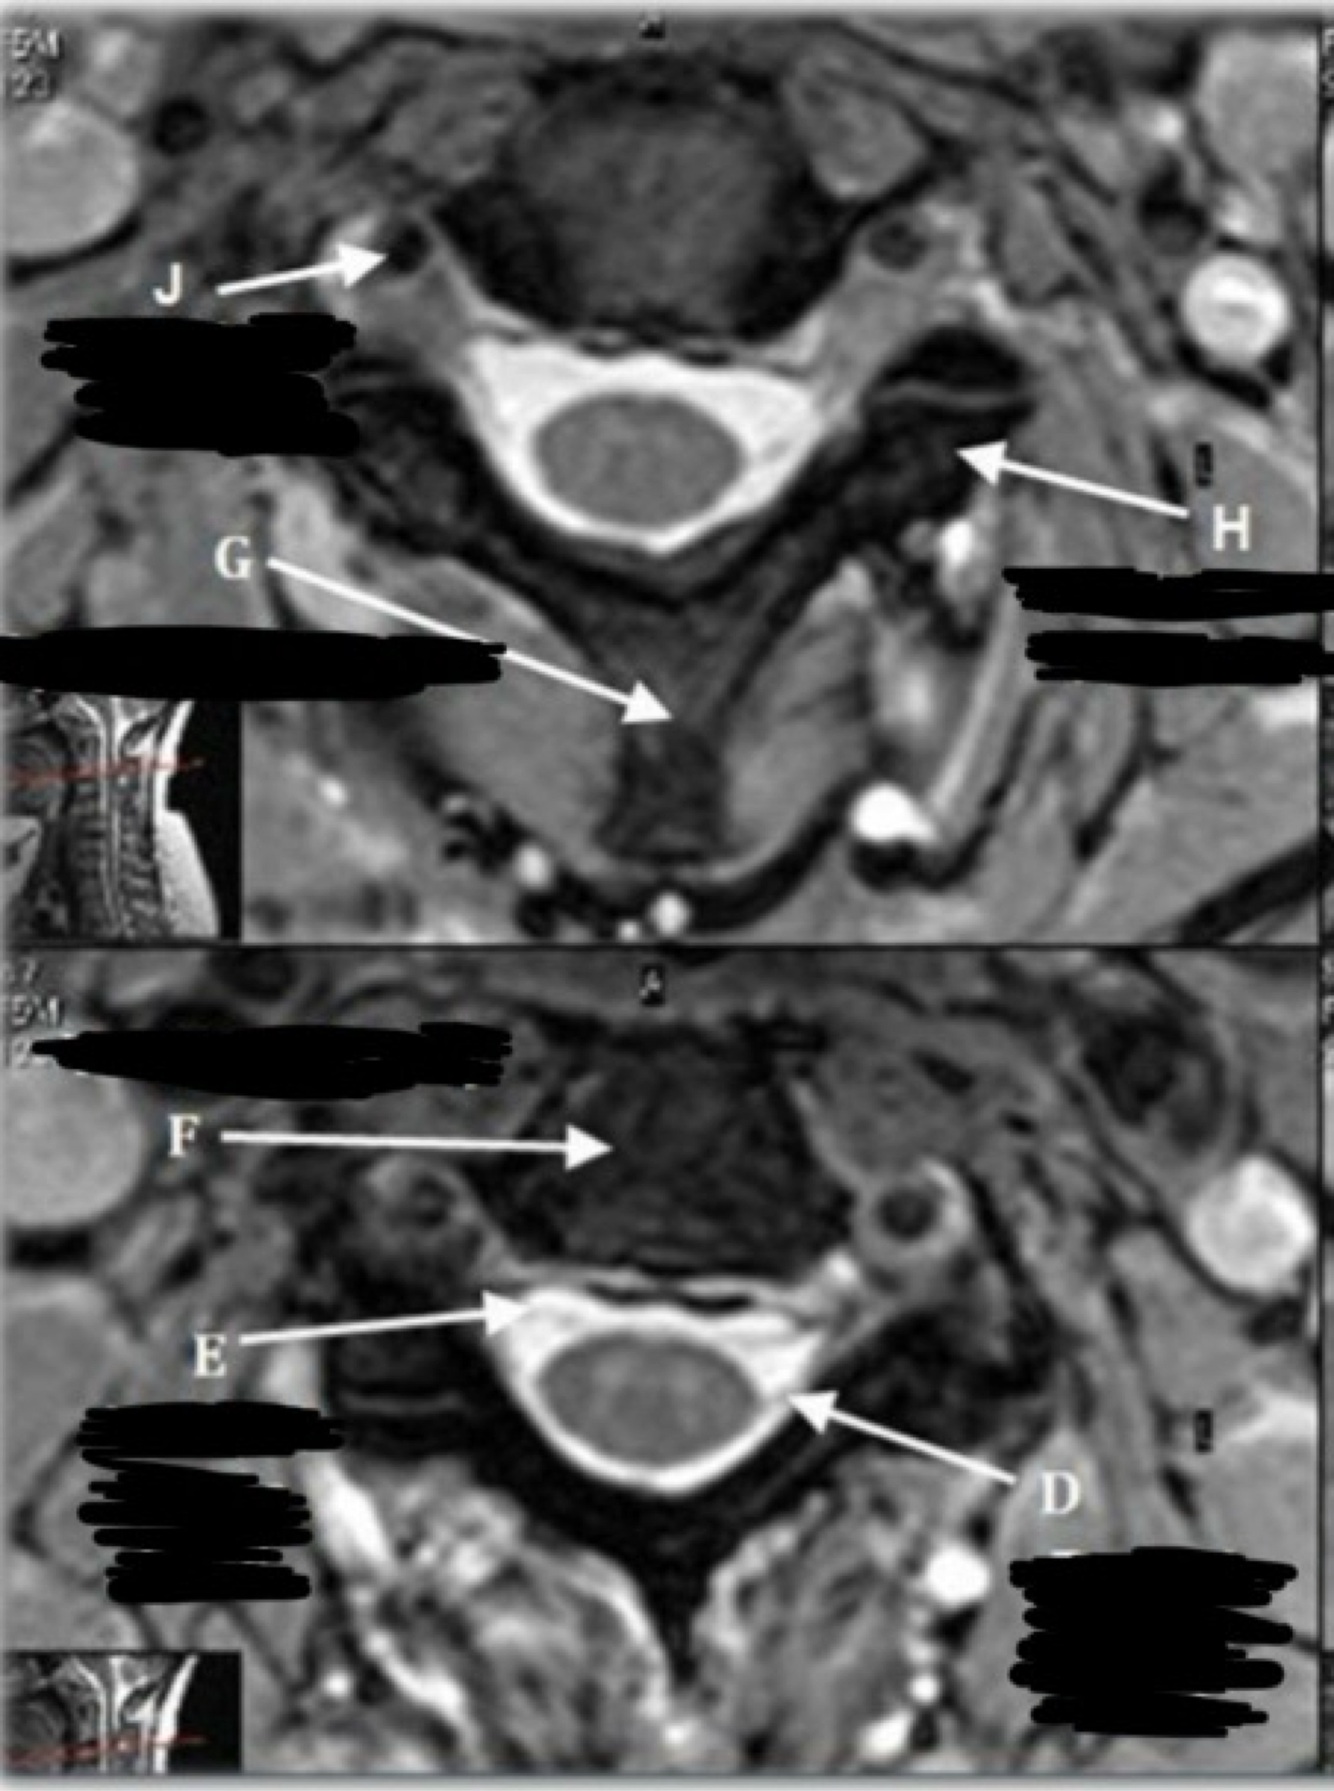

10

What is letter A?

CSF

11

What is letter B?

SPINAL CORD

12

What is letter C?

LAMINA

13

What is letter D?

DORSAL NERVE ROOT

14

What is letter E?

VENTRAL NERVE ROOT

15

What is letter F?

VERTEBRAL BODY

16

What is letter G?

SPINOUS PROCESS

17

What is letter H?

TRANSVERSE PROCESS

18

What is letter J?

VERTEBRAL ARTERY